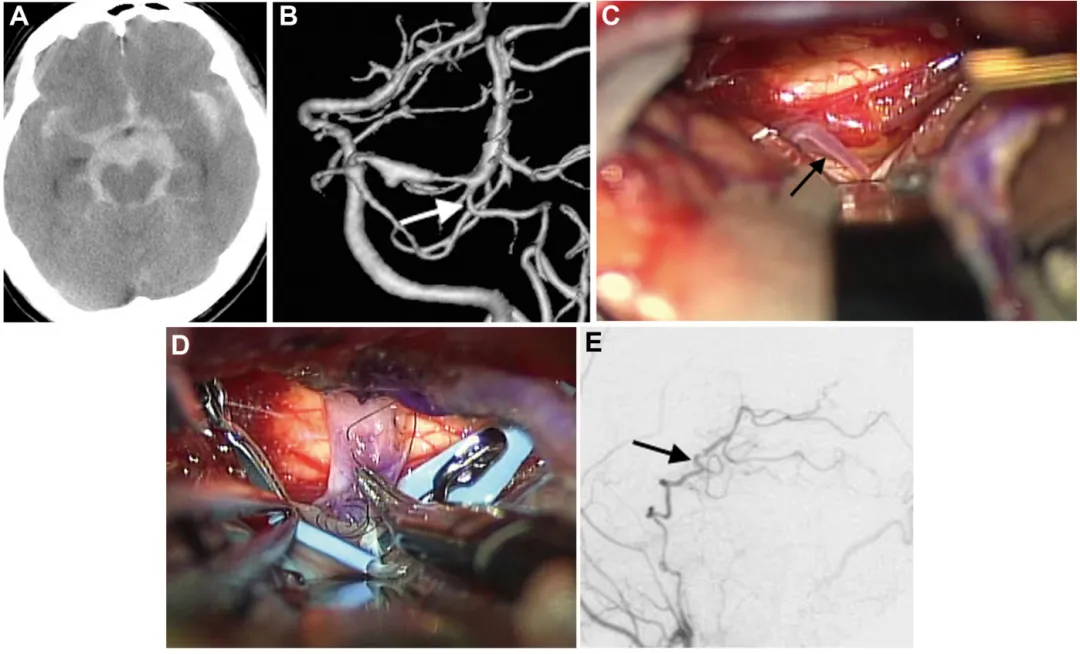

一位43岁男性,右侧P2段梭形动脉瘤保守观察11年间持续增大,破裂风险增高(图A、B)。通过右侧颞下入路,医生成功将颞浅动脉与P3段吻合(图C、D),然后安全地孤立了动脉瘤。术后患者无任何神经功能障碍,一年后复查显示“新血管”工作良好(图E、F)。

病例1:术前影像(A、B)、术中照片(C、D)及术后血管造影(E、F)

A.MRI T2加权像显示右侧环池内血栓性动脉瘤,压迫梭状回;

B.三维CT血管造影显示右侧P2段梭形动脉瘤,颞后动脉及P3段起始部自动脉瘤远端发出(圆圈标注);

C、D.用橡胶片调整从深部向表面走行的P3段位置;

E、F.术后血管造影显示通过分流血管,右侧大脑后动脉供血区血流良好,动脉瘤成功行外科孤立术。

病例二(破裂动脉瘤)

一位47岁男性因蛛网膜下腔出血入院(图A),后续检查发现是左侧P1-P2段的夹层动脉瘤在“作祟”(图B)。情况危急,医生同样通过左侧颞下入路,选择后颞动脉作为受体(图C、D),成功完成搭桥和孤立术。患者康复出院,一年后恢复如常。

病例2:术前影像(A、B)、术中照片(C、D)及术后血管造影(E)

A.CT显示弥漫性蛛网膜下腔出血,左侧脑桥前池增厚明显;

B.出血后18天血管造影显示左侧P1-P2段扩张伴狭窄特征,颞后动脉自狭窄病变远端发出(箭头标注);

C、D.选择颞后动脉(箭头标注)作为受体动脉,经左侧颞下入路用连续缝合行颞浅动脉-颞后动脉吻合;

E.术后1周颈外动脉血管造影显示,通过分流血管,整个左侧大脑后动脉供血区血流良好(箭头标注)。